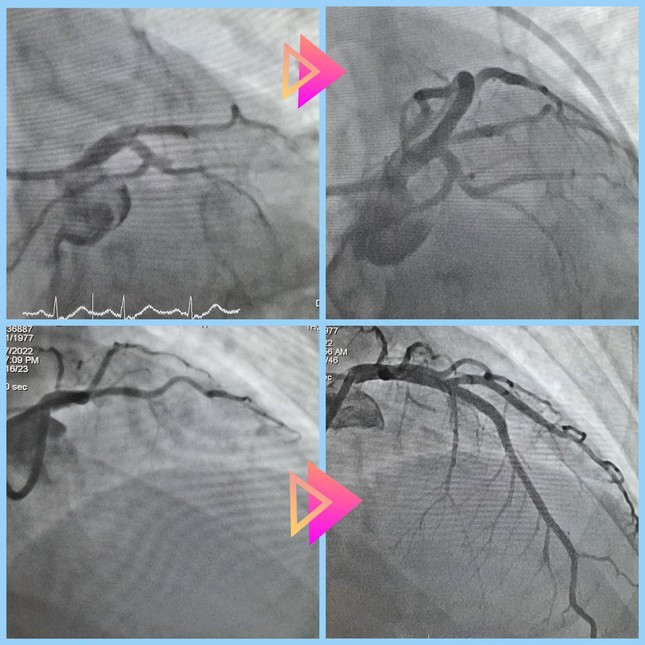

Mạch máu của bệnh nhân trước (hình trên) và sau can thiệp (hình dưới) nhồi máu cơ tim cấp.

Bằng thiết bị chuyên dụng, các bác sĩ đã hút huyết khối, đặt stent tại vị trí tắc mạch, tái thông thành công dòng chảy mạch vành.

BS Nguyễn Thái Anh, khoa Hồi sức Tim mạch cho biết, trong quá trình can thiệp, ê kíp ghi nhận người bệnh bị tắc hoàn toàn nhánh động mạch vành liên thất trước.